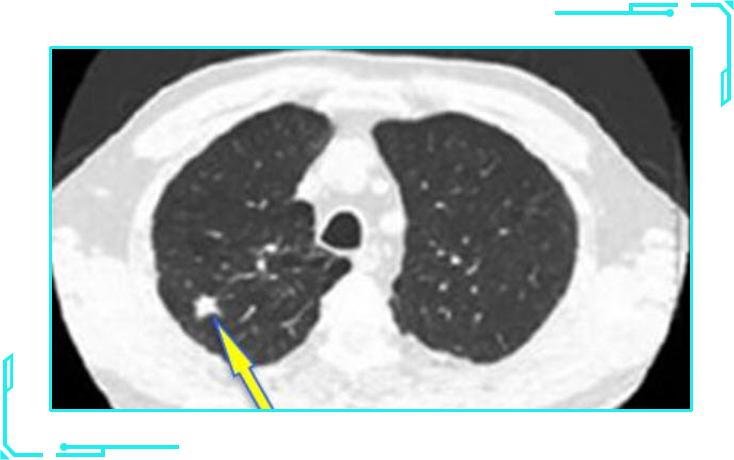

1纯磨玻璃结节

纯磨玻璃结节,影像表现像磨砂玻璃一样,看起来影像比较虚。